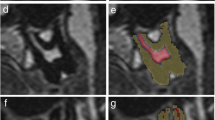

Dentine, enamel, and cementum could not be differentiated based on T2 signal intensity in our MRI sequence. These tissues were collectively segmented as hard tooth tissue, as shown in Fig. 1 b–g. Soft tissues were differentiated based on T2 signal intensity as high signal soft tissue and low signal soft tissue. Based on previous experience with ground sections, we believe that high signal soft tissue and low signal soft tissue correspond to pulp and predentine, respectively.

Axial MRI shows correct bilateral placement of dental cotton rolls soaked in water (arrows) between the molars (a). The cotton rolls delineated the upper and lower molars and stabilized the bite. Axial MRI through the upper jaw shows unsegmented (b) and segmented (c) tooth 26 and 27. Grey for hard tooth tissue, yellow for low signal soft tissue and red for high signal soft tissue. Lower and upper thresholds were set at 0 and 63 for hard tooth tissue, 64 and 100 for low signal soft tissue and ≥101 for high signal soft tissue. Sagittal MRI through the upper jaw shows unsegmented (d) and segmented (e) tooth 26 and 27. Grey for hard tooth tissue, yellow for low signal soft tissue and red for high signal soft tissue.3D of the entire tooth 46 and 47 (f) and 3D rendering of the segmentation (g), with a wedge of approximately one half removed to visualize the high signal soft tissue. Grey for hard tooth tissue, yellow for low signal soft tissue and red for high signal soft tissue

Lower and upper T2 signal intensity thresholds were set at 0 and 63 for hard tooth tissue, 64 and 100 for low signal soft tissue, and ≥101 for high signal soft tissue.